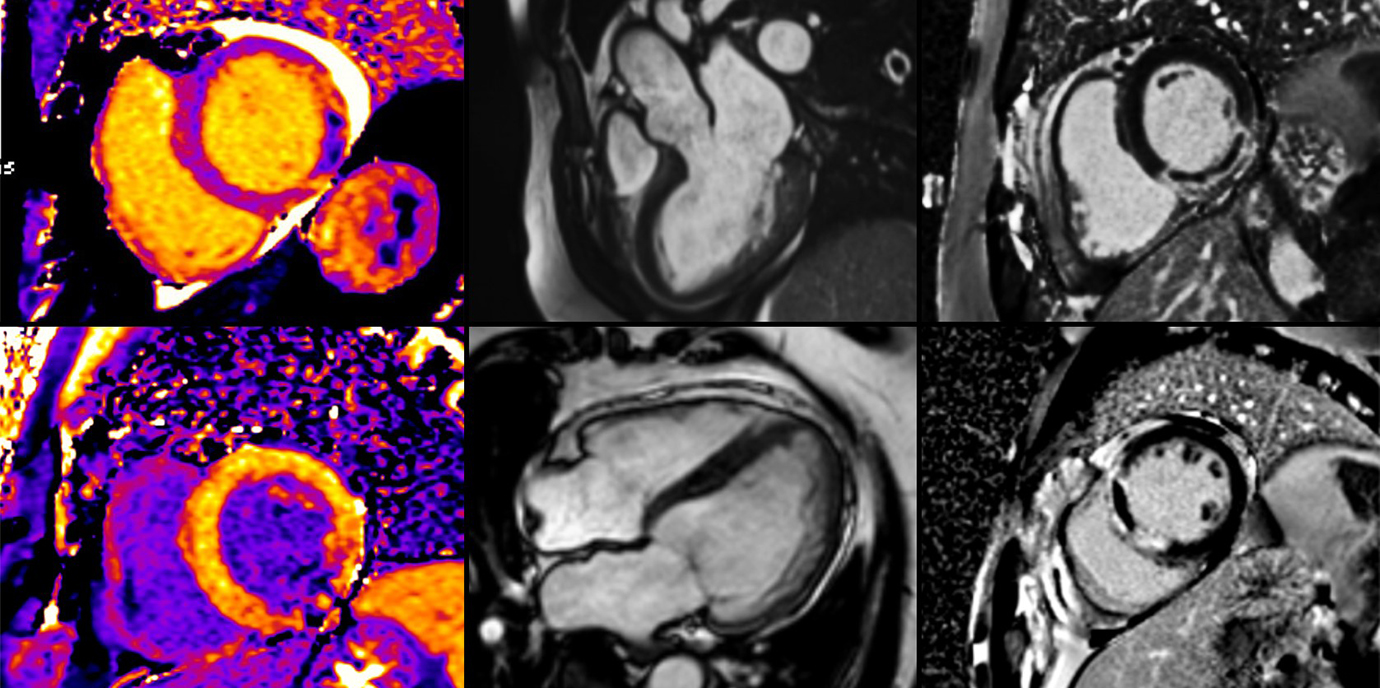

Kardiale MRT liefert umfassendes Bild

„Wir konnten zeigen, dass es besonders während der COVID-19 bedingten Restriktionen zu einer Zunahme der Infarktgröße gekommen ist“, beschreibt Kardiologe Sebastian Reinstadler die zentrale Erkenntnis der Innsbrucker Studie, für die insgesamt 474 Patient:innen einer kardialen MRT wenige Tage nach dem Akutereignis unterzogen wurden. Die kardiale Magnetresonanztomographie (MRT) ist der nicht-invasive Goldstandard für eine umfassende Charakterisierung des Myokardgewebes nach einem STEMI, mit der sich insbesondere die Schwere der Gewebsschädigung, ausgedrückt als Infarktgröße, mikrovaskuläre Obstruktion (MVO) und intramyokardiale Blutung (IMH), sehr genau bestimmen lässt. Sowohl die Größe als auch der Schweregrad des Infarktes, der in der ersten Woche nach einem STEMI mittels kardialer MRT dargestellt werden kann, stehen in sehr engem Zusammenhang mit der funktionellen Erholung des Herzmuskels, einer zukünftigen chronischen Herzinsuffizienz und letztlich auch der kardiovaskulären Mortalität.